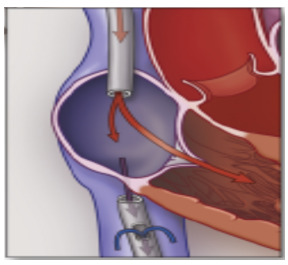

ECMO工作原理

通过中心静脉置管将血液引流出来,再通过离心泵驱动血液向前流动,然后通过膜肺进行气体交换,交换后的血液在泵的推动下可回到静脉,即为VV-ECMO,也可回到动脉,即为VA-ECMO。2020年,随着新冠疫情在全球大流行,ECMO的应用在国内得到了迅猛发展,很多医院以及各亚专科ICU都开始陆续开展ECMO工作,ECMO也救治了很多危重症患者。

图片